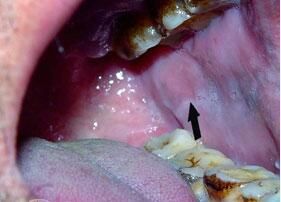

口腔扁平苔藓现在治疗起来还没有什么药,口腔扁平苔藓患者要尽量的减少发病因素,保持平稳的心态,将口腔扁平苔藓病情稳定下来,再通过积的治疗逐渐好转。同时口腔扁平苔藓还会伴发其他的疾病,我们一起来看看吧。

口腔扁平苔藓并发疾病有哪些